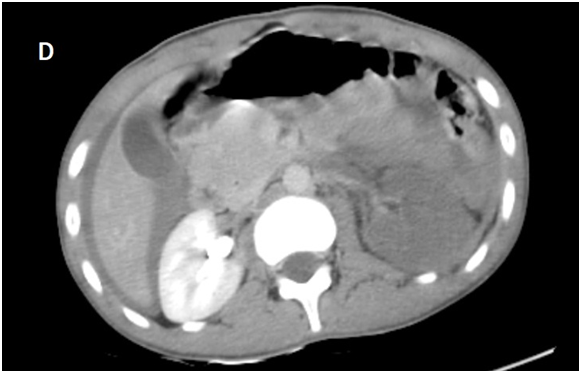

Figure 1D Late acquisition of contrast enhanced CT abdominal scan.

A Contrast enhanced computed tomography control was performed at D+7 showing a sudden stop of the Contrast progression at the initial portion of the left renal artery, leading to total left renal ischemia, with stability of the perirenal hematoma, spleen injury and no extravasation at the late acquisitions.